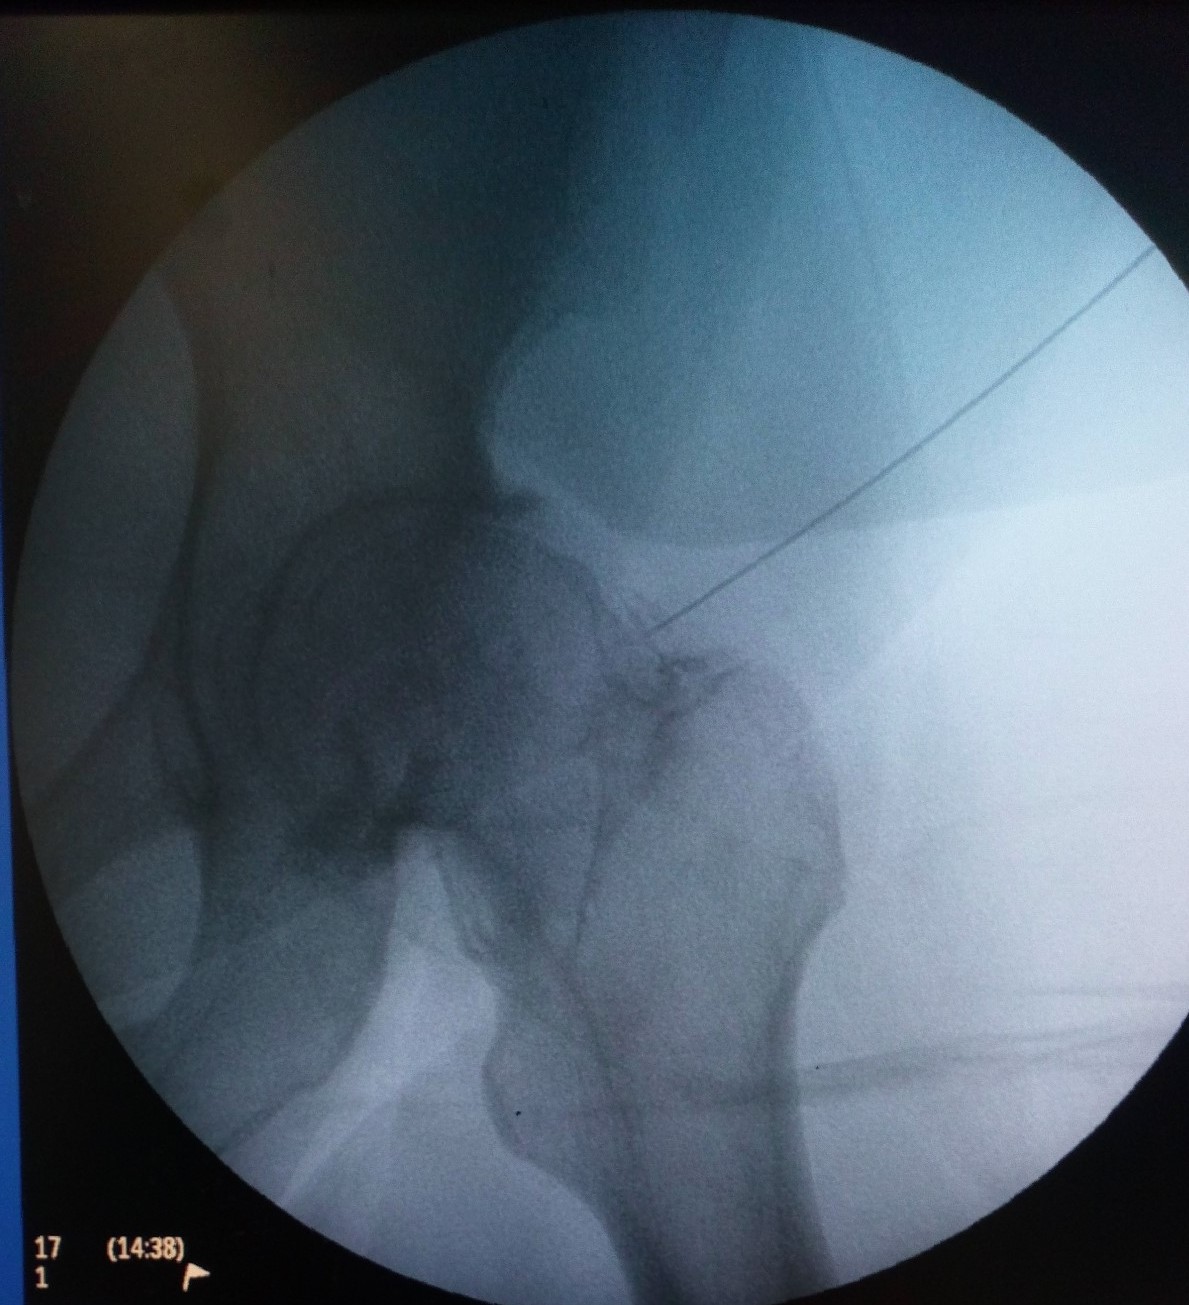

Ασθενής με οστικό οίδημα αριστερού ισχίου

Ασθενής 51 ετών, με αιφνίδιο άλγος από μηνός συνεχώς επειδυνούμενο. Η μαγνητική τομογραφία έδειξε ότι υπάρχει εκτεταμένο οστικό οίδημα αριστερού ισχίου (βέλος). Πραγματοποιήθηκε έγχυση ισχίου με υαλουρονικό και παυσίπονα. Ο ασθενής ένιωσε άμεσα ανακούφιση με πλήρη υποχώρηση των συμπτωμάτων που διατηρείται έως σήμερα 1.5 χρόνο μετά.